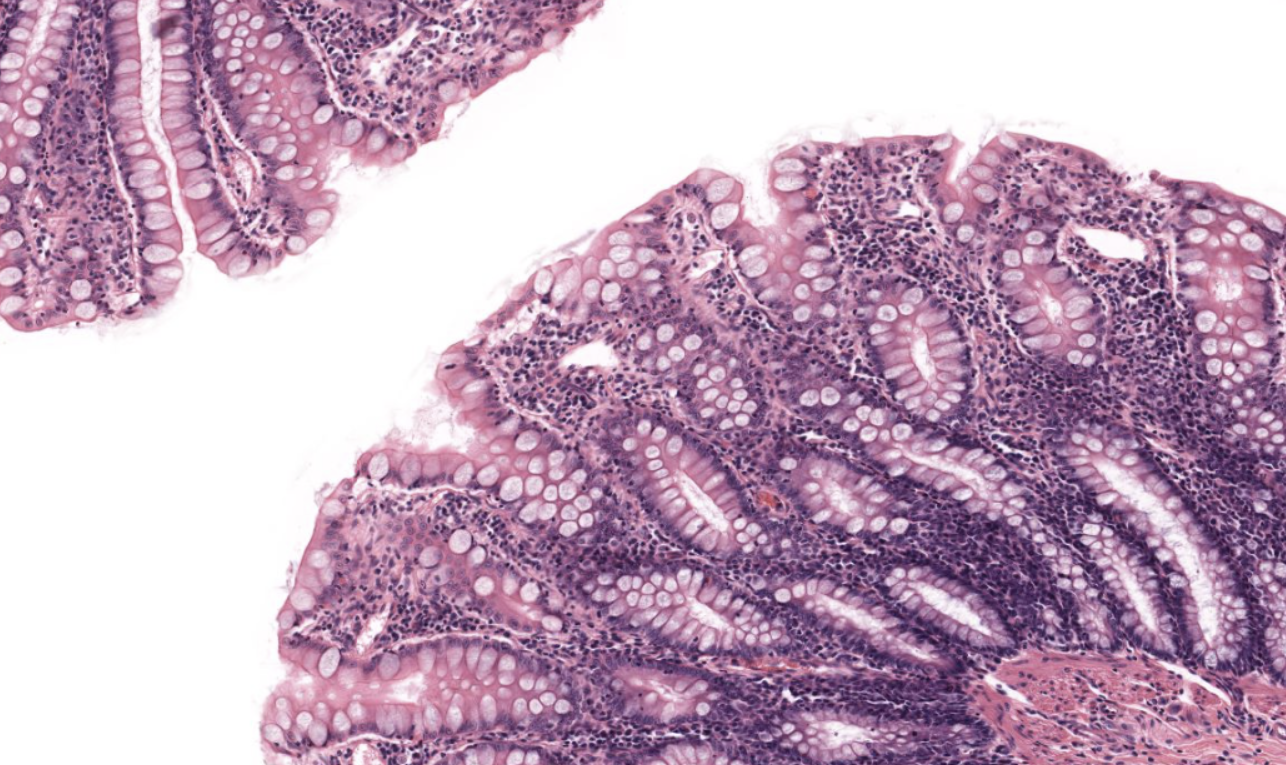

Colon

NOTICE: THE LARGE NUMBER OF GOBLET CELLS WHICH ARE LIGHTER IN COLOR DUE TO THE WATER CONTENT NEEDED TO PROTECT FROM SOLID WASTE, THE MUCOSA ALSO HAS MORE UNIFORM RIDGES

Small Intestine

NOTICE: THE FINGER-LIKE PROJECTIONS (VILLI) WITH OPEN SPACE INSIDE AND A FEW GRAY/BLUE GOBLET CELLS ALONG THE SIDES (NOT AS MANY AS LARGE INTESTINE